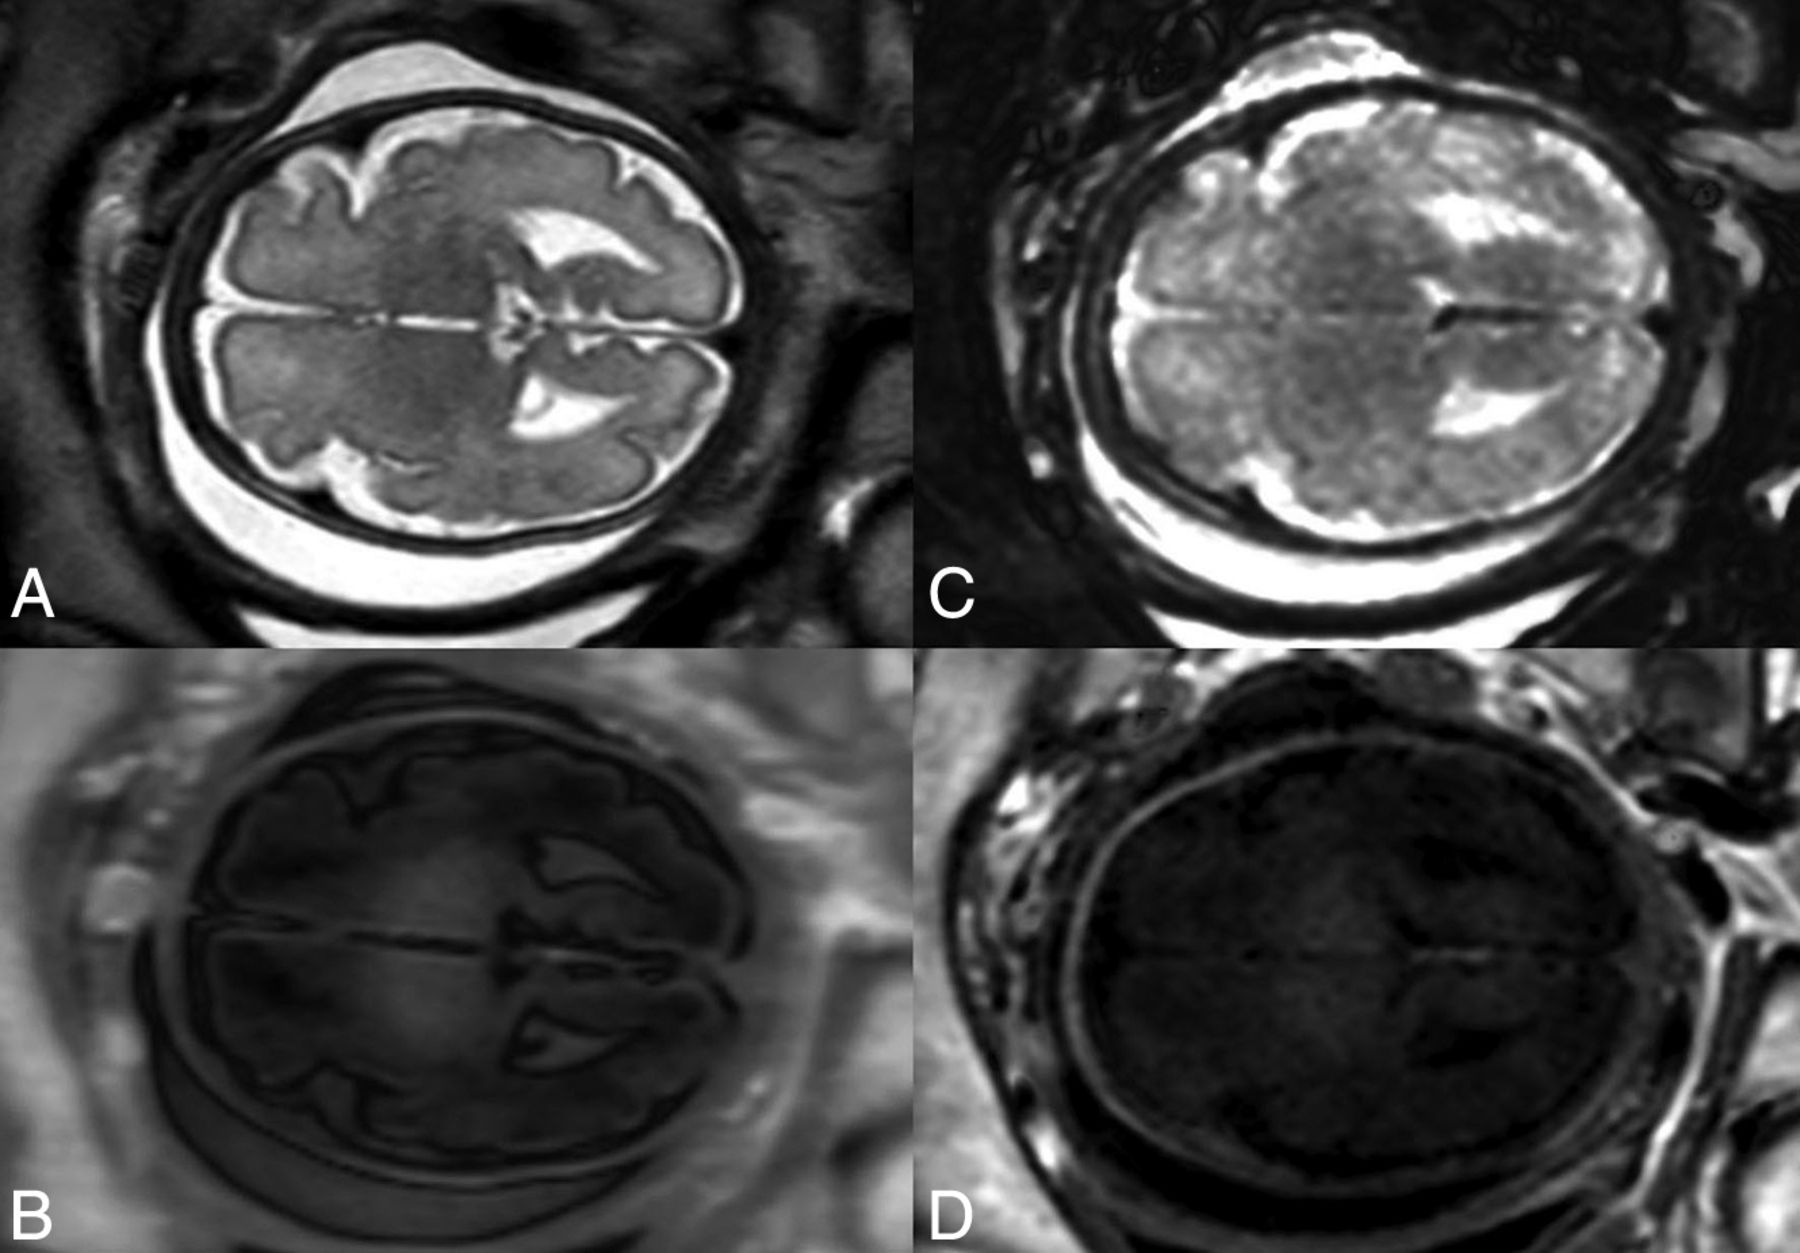

Imaging was performed in accordance with the fetal MR imaging guidelines of the International Society of Sonography in Obstetrics and Gynecology.20 All fetuses were examined using a standardized fetal MR imaging protocol of the brain (Online Supplemental Data) on the same Ingenia 1.5T MR imaging system (Philips Healthcare) equipped with a body coil. An MDME sequence (Online Supplemental Data) (acquisition time: 3 minutes and 20 seconds) was acquired (axial plane) by applying 2 repeat acquisition phases: phase a: saturation of 1 section by a section-selective saturation pulse (flip angle = 120°); and phase b: section-selective excitation pulses (flip angle = 90°) and section-selective refocusing pulses (flip angle = 180°) to generate a train of spin-echoes for another section.17,21,22 Via the mismatch between the saturated section and the image section, a matrix with a variety of effects of R1/R2 was acquired.21,22 Echo-trains, characterized by different saturation delays, were used to estimate T1-/T2-relaxation parameters.17,21,22 The T1-relaxation constants allowed the local radiofrequency field (B1) to be calculated.21 On the basis of the acquired relaxation parameters and B1, the PD can be computed.17 SyMRI-based MDME postprocessing (postprocessing time: <1 minute) was applied to generate conventional MR imaging contrasts (Fig 1) and quantitative MR imaging maps (Fig 2) for qualitative and quantitative analysis. Color-coded voxels, according to the physical MR imaging properties, were used to generate quantitative maps.21

Conventionally acquired (A and B) and SyMRI-generated (C and D) fetal MR image data of comparable SIs: T2-weighted (A); snapshot inversion recovery (B); T2-weighted STIR (TR = 15,000 ms, TE = 100 ms, TI = 300 ms) (C); and T1-weighted inversion recovery (TR = 2500 ms, TE = 10 ms, TI = 1050 ms) (D). Presentation of SyMRI-generated MR imaging contrasts based on the default software settings for TR, TE, and TI.